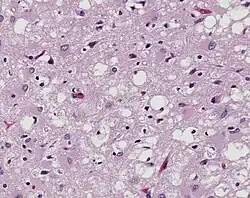

Magnificado 100× y teñido. Esta microfotografía del tejido cerebral muestra la presencia de los prominentes cambios espongióticos en la corteza, con la pérdida de neuronas en un caso de una variante de la enfermedad de Creutzfeldt-Jakob (vCJD).

Los priones son proteínas mal plegadas que son transmisibles y pueden influir en el plegamiento anormal de las proteínas normales del cerebro. No contienen ADN ni ARN y no pueden replicarse más que para convertir las proteínas normales ya existentes al estado mal plegado. Estas proteínas plegadas anormalmente se encuentran característicamente en muchas enfermedades neurodegenerativas, ya que agregan el sistema nervioso central y crean placas que dañan la estructura del tejido. Esto crea esencialmente "agujeros" en el tejido. Se ha descubierto que los priones se transmiten de tres formas: obtenida, familiar y esporádica. También se ha descubierto que las plantas desempeñan el papel de vector de los priones. Hay ocho enfermedades diferentes que afectan a los mamíferos y que están causadas por priones, como la tembladera, la encefalopatía espongiforme bovina (enfermedad de las vacas locas) y la encefalopatía espongiforme felina (EEF). También hay diez enfermedades que afectan a los humanos, como la enfermedad de Creutzfeldt-Jakob (ECJ).[10]​ y Insomnio familiar fatal (FFI).